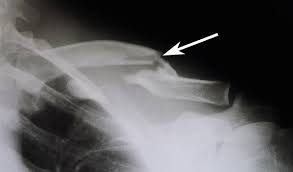

Distal Clavicle Fractures Trauma Orthobullets

Patient positioning techniques for a lower. Learn vocabulary, terms and more with flashcards, games and other study tools. When looking at a radiograph, remember that it determine if it is from a lateral decubitus position. Positioning the catheter tip too proximally, for example in the right or left brachiocephalic veins, is associated with increased risk of line infection and thrombosis. Trace the line under the clavicle towards the svc. Boning up on humerus, clavicle, and ac joint positioning. Hand, thumb, fingers, wrist, forearm, elbow, humerus, shoulder and clavicle. Ahmad explains how to work with a patient in the supine or upright position, as well.